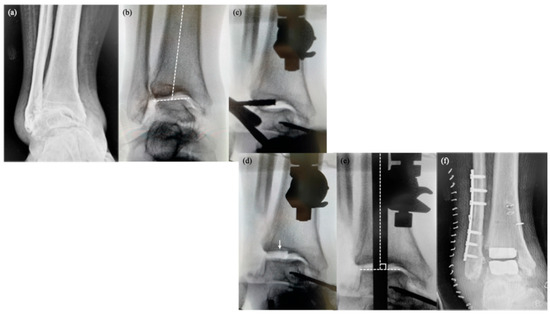

Figure 5.

Surgical sequence of total ankle arthroplasty using the conventional anterior approach. (a) Preoperative condition in varus-type ankle osteoarthritis. (b) Independent bone preparation of the tibial and talar surfaces using the tibial shaft and native talar surface as respective references. (c) Independent implantation of tibial and talar components. (d) Adjustment of polyethylene insert thickness to lower the talus and prevent abnormal contact at the lateral gutter. In severe varus, medial soft tissue contracture often limits talar lowering, necessitating aggressive medial ligament release. (e) Additional procedures, such as medial malleolar osteotomy and/or tibialis posterior tendon lengthening, may be performed as required. The arrow indicates the extension of the medial malleolus.

Severe varus deformity of the ankle, particularly deformities exceeding 15 degrees, is generally considered a contraindication to TAA. Such deformities tend to result in misalignment during implantation and an imbalance in soft tissue tension. These factors increase the risk of edge loading, which may eventually lead to early implant failure [

Figure 5), the position of the talus needs to be adjusted to maintain the physiological congruity of the lateral gutter articulation.

Moreover, significant talar lowering is required to achieve orthogonal alignment in cases of severe varus ankles. As talar lowering is often restricted by medial soft-tissue contracture, aggressive medial ligament release is frequently necessary, and additional procedures including medial malleolar osteotomy and/or tibialis posterior tendon lengthening may be employed as needed [

1,

15]. However, as the lateral approach utilized with the TM Ankle system involves fibular osteotomy (

Figure 6), the congruity of the lateral gutter can be optimized by adjusting the height of the lateral malleolus, specifically by shortening the fibular length during internal fixation of the osteotomy site.